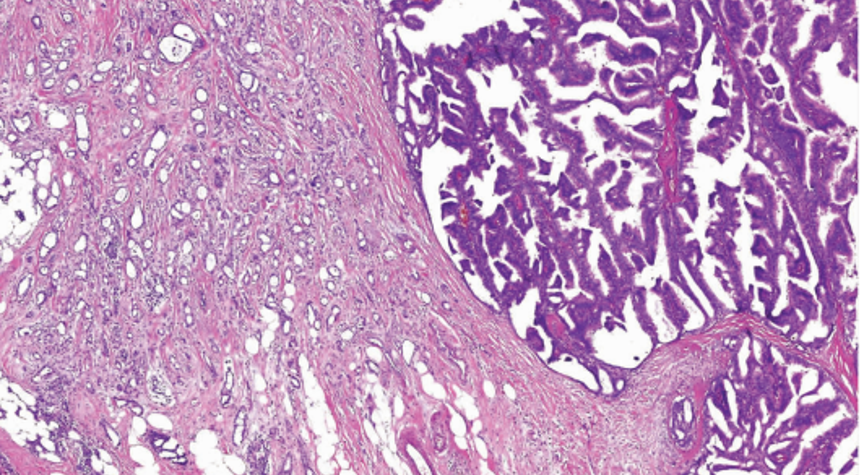

2、实性乳头状癌伴浸润:轮廓圆滑的结节,伴有浸润性成分,包括粘液癌,NET,浸润性癌(NST)

SPC+富于细胞的黏液癌

原位SPC的乳头轴心及导管周边的肌上皮可以存在,也可以不同程度减少。原位SPC可被视为导管原位癌的特殊亚型,因此,临床可以按导管原位癌处理。极端状态下,导管周边的肌上皮可以完全缺失,此时可被称为膨胀性或推挤性浸润,其形态与原位SPC高度相似。研究显示,膨胀性浸润的SPC通常不发生转移,因此仍可按导管原位癌处理。

当在原位SPC的背景上,部分原位SPC轮廓变得不规则,或呈地图、锯齿状,并出现促纤维反应,或浸润脂肪,可称为原位SPC伴浸润(毁损性浸润),这时需按浸润癌处理。